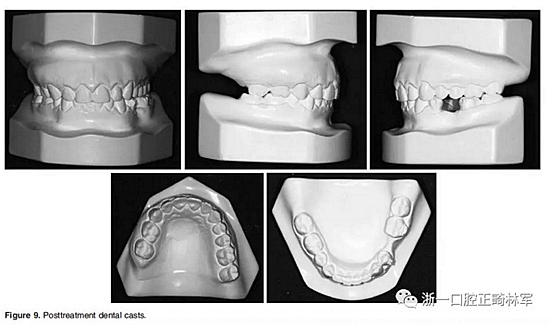

四、完成

在治療結(jié)束時,面部基本對稱(Figure 7)。上中線與面中線重合,下中線向左偏0.5mm,傾斜的合平面得到矯正,獲得了良好的咬合關(guān)系,具有正常的覆合和覆蓋,留下7mm的空間用于植入左下前磨牙(Figure 8、9)。

全景片顯示牙根平行度良好、無吸收。此外,在左下第二前磨牙的區(qū)域獲得了用于植入種植體修復的良好空間。頭顱側(cè)位片和疊加顯示,上下切牙傾斜度以及前后和垂直向位置的變化也很大(Figure 10、11; Table 1)。